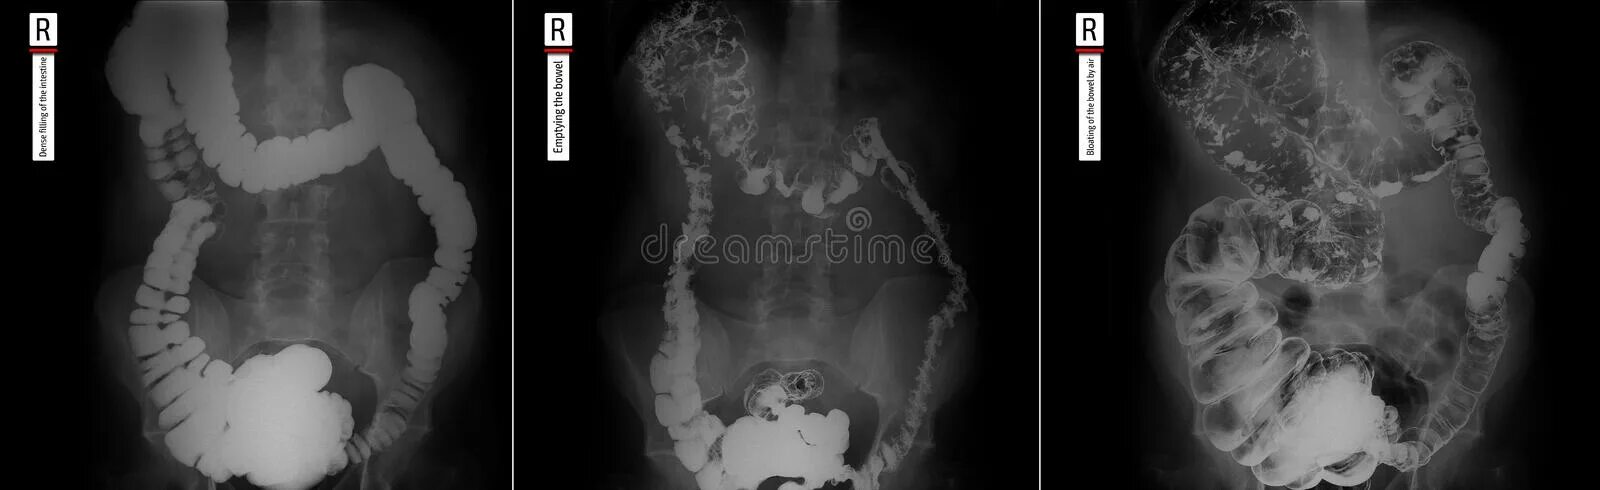

Долихосигма кишечника у ребенка